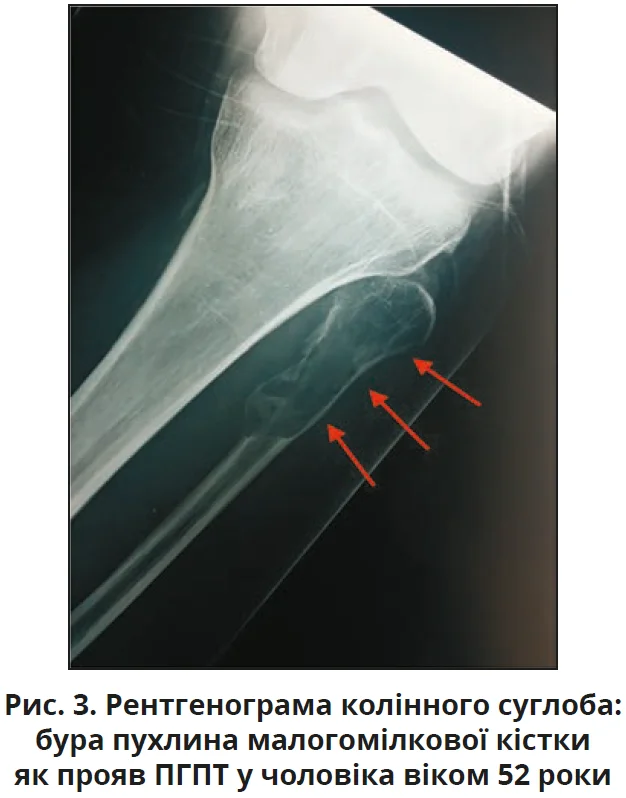

На сьогодні класичні кісткові прояви фіброзно-кістозного остеїту є рідкісними (<2%). Частіше це ускладнення трапляється при вторинному або третинному гіперпаратиреозі внаслідок хронічної ниркової недостатності. Основними симптомами є слабкість, біль у кістках, патологічні переломи; можливі неспецифічні симптоми (закрепи, нейропсихічні симптоми, нефролітіаз). Радіологічні ознаки: «сіль/перець» або «матове скло» в черепі (демінералізація); резорбція дистального кінця ключиці та фаланг; кісткові кісти, бурі пухлини, остеокластоми, дифузна остеопенія. Бурі пухлини – неонкологічні утворення, що складаються з остеокластів, грануляційної, фіброзної та судинної тканин з відкладенням гемосидерину й не повністю мінералізованої кістки внаслідок надмірної активності остеокластів; типова локалізація: щелепи, череп, таз, ключиця, ребра, стегна, хребет. Пухлини можуть бути одиничними або множинними (рис. 3), при візуалізації часто імітують доброякісні (кісти, фіброзна дисплазія) або злоякісні ураження, але біль за них менш інтенсивний, супроводжується типовими ознаками ПГПТ. Значно знижена МЩКТ відновлюється після успішної операції. При тяжкому ПГПТ значно підвищені рівні кальцію та ПТГ у сироватці крові. Через те що ПГПТ характеризується посиленням ремоделювання кісток, підвищуються біохімічні маркери як остеосинтезу (ЛФ, остеокальцин), так і резорбції кісток (N-термінальний телопептид [NTX], C-телопептид [CTX]).